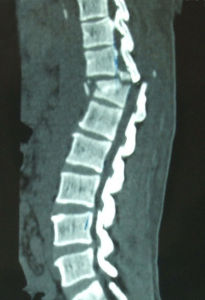

閉合性骨折的X線檢查X線檢查對閉合性骨折的診斷和治療具有重要價值。凡疑為閉合性骨折者應常規進行X線拍片檢查,可以顯示臨床上難以發現的不完全性閉合性骨折,深部的閉合性骨折、關節內閉合性骨折和小的撕脫性閉合性骨折等。即使臨床上已表現為明顯閉合性骨折者,X線拍片檢查也是必要的,可以幫助了解閉合性骨折的類型和閉合性骨折端移位的情況,對於閉合性骨折的治療具有重要指導意義。

閉合性骨折的X線檢查一般應拍攝包括臨近一個關節在內的正、側位片,必要時並拍攝特殊位置的X線片,如掌骨和跖骨拍正位及斜位片,跟骨拍側位和軸心位,腕舟狀骨拍正位和蹀位,有時不遺確定損傷情況時,尚需拍對側肢體相應部位的X線片,以便進行對比,值得注意的是,有些輕微的裂縫閉合性骨折,急診派片未見明顯閉合性骨折線如臨床症狀較明顯者,應於傷後2周拍片複查,此時,閉合性骨折端的吸收常可出現閉合性骨折線,如腕舟骨閉合性骨折。